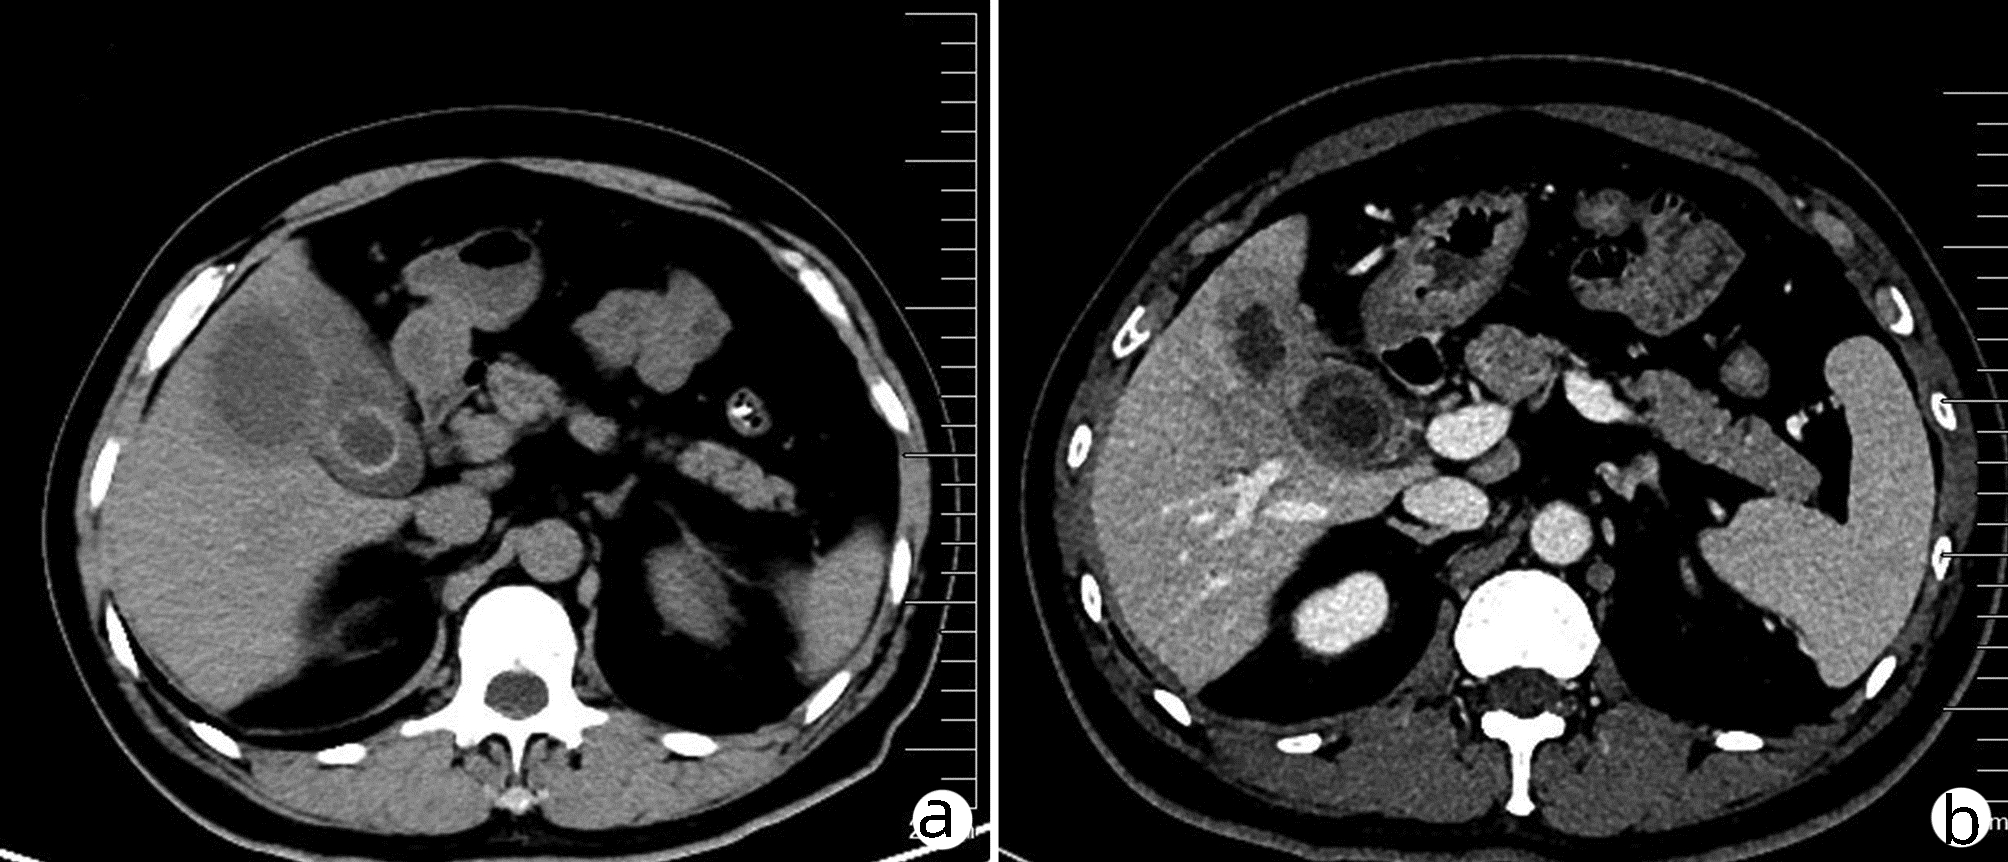

局部栓塞联合靶向免疫综合治疗肝肉瘤样癌1例报告

雷进, 张林枝, 陆荫英, 陈博文, 左石

2022, 38(4): 880-882. DOI: 10.3969/j.issn.1001-5256.2022.04.026

摘要(1323) HTML (453) PDF (3487KB)(82)

摘要: